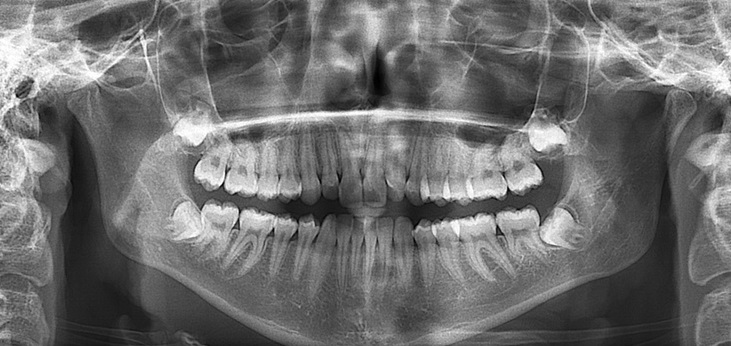

- Ортопантомограмма — это обзорный снимок полости рта, дающий максимальную информацию о состоянии тканей. Стоимость процедуры составляет от четырехсот девяноста рублей до двух тысяч шестисот рублей.

- Снимок помогает врачу определить:

- строение зубных рядов;

- структуру мягких тканей и зубов;

- стадии прорезки зубов мудрости;

- состояние пазух носа и верхнечелюстных суставов;

- качество пломб и пломбированных каналов;

- патологию мягких тканей;

- наличие кист и скрытого кариеса.